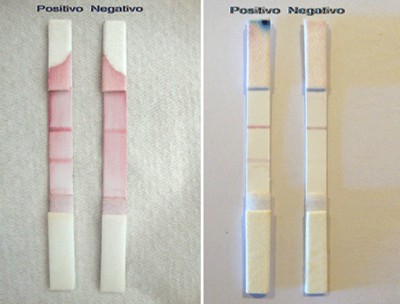

Investigadores Argentinos desarrollan un diagnóstico rápido del Síndrome Urémico Hemolítico

Parecido al test de embarazo, se visualizan dos bandas ante la presencia de la toxina que produce esa enfermedad. Todavía está en fase experimental.

Un dispositivo similar al de los test de embarazo sirve para...